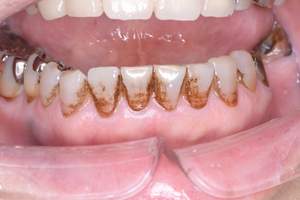

治療前 1

治療後 1

治療前 2

治療後 2

治療前 3

治療後 3

| 年齢 | 58歳・女性 |

|---|---|

| 主訴 | 前歯の着色除去希望 |

| 治療内容 | エアフロー |

| 費用 | 合計:5,500円 (2024年8月現在) |

| 治療期間 | 60分 |

| リスク・副作用 | 呼吸器疾患のある方や放射線治療を行っている方、ナトリウム摂取制限を必要とする方や妊娠中の方は処置を受けられないことがあります。 施術を受ける際、舌や歯肉に当たった粒子でチクチクとした痛みを感じることがあります。 |

| 治療方針 | 歯周病と虫歯の治療を担当医と相談し進めていく予定です。 |

| 担当者所見 | 約4年ぶりの来院でした。他の歯医者に行っても満足いくクリーニングをしてもらえず悩んでいる様子でした。問診時には手で口元を隠すようにお話されていましたが、エアフロー後は笑顔でお話するようになっていました。 |